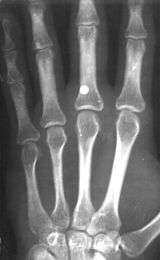

BB gun injury: pellet penetrates inside a hand

Most BB-firing airguns can shoot faster than 60 m/s (200 ft/s). Some airguns have the ability to fire considerably faster, even beyond 170 m/s (560 ft/s). Although claims are often exaggerated, a few airguns can actually fire a standard 0.177 caliber lead pellet faster than 320 m/s (1,000 ft/s), but these are generally not BB-firing guns.

A BB with a velocity of 45 m/s (150 ft/s) has skin piercing capability, and a velocity reaching 60 m/s (200 ft/s) can fracture bone.[4] The potential exists for killing someone; this potential increases with velocity, but also rapidly decreases with distance. The effective penetrating range of a BB gun with a muzzle velocity of 120 to 180 metres per second (390 to 590 ft/s) is approximately 18 metres (60 ft). A person wearing jeans at this distance would not sustain serious injury. However, even at this distance a BB still might penetrate bare skin, and even if not, could leave a severe and painful bruise. The maximum range of a BB gun in the 120 to 180 m/s (390 to 590 ft/s) range is 220 to 330 metres (240 to 360 yd), provided the muzzle is elevated to the optimum angle.